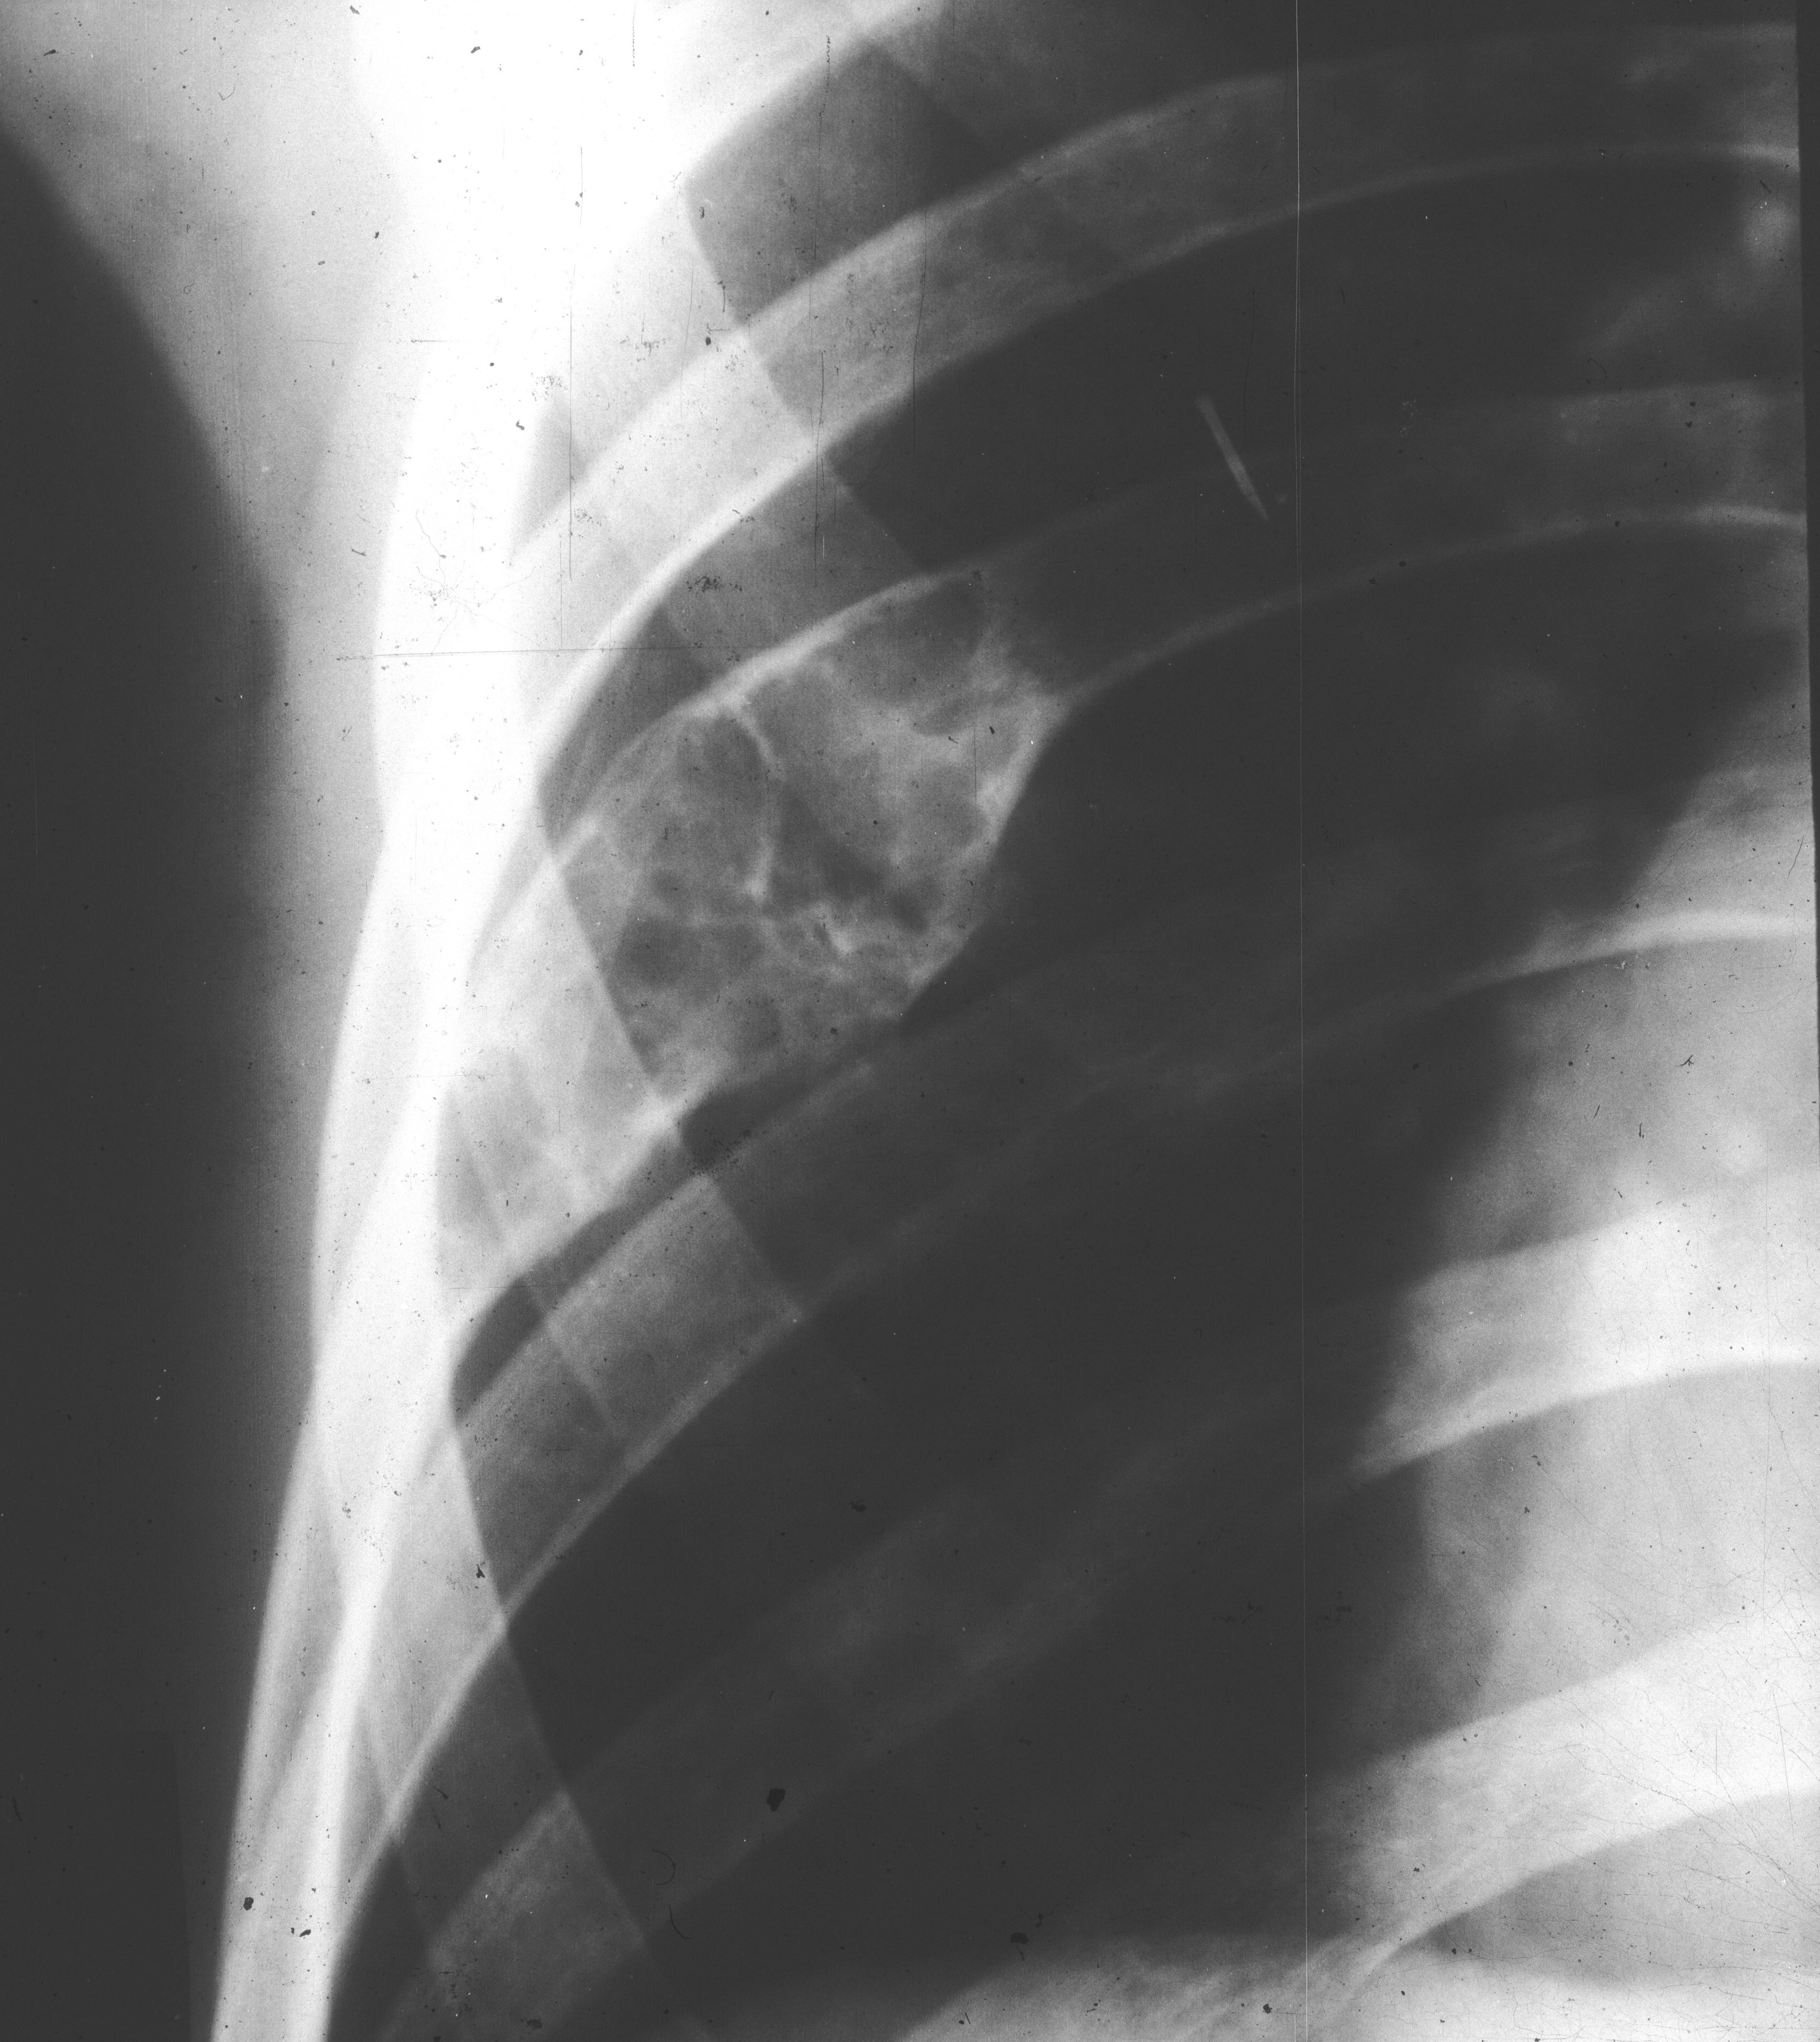

Uniform expansion with lobulated and thin cortex is often noted (Figure 10).

Figure 10: FD – Right 5th rib shows localized expansion with lobulation of the cortex The clavicles are rarely affected. The lesion can be a mixture of lysis and osteolysis or entirely lytic and expanding (Figure 11ab).